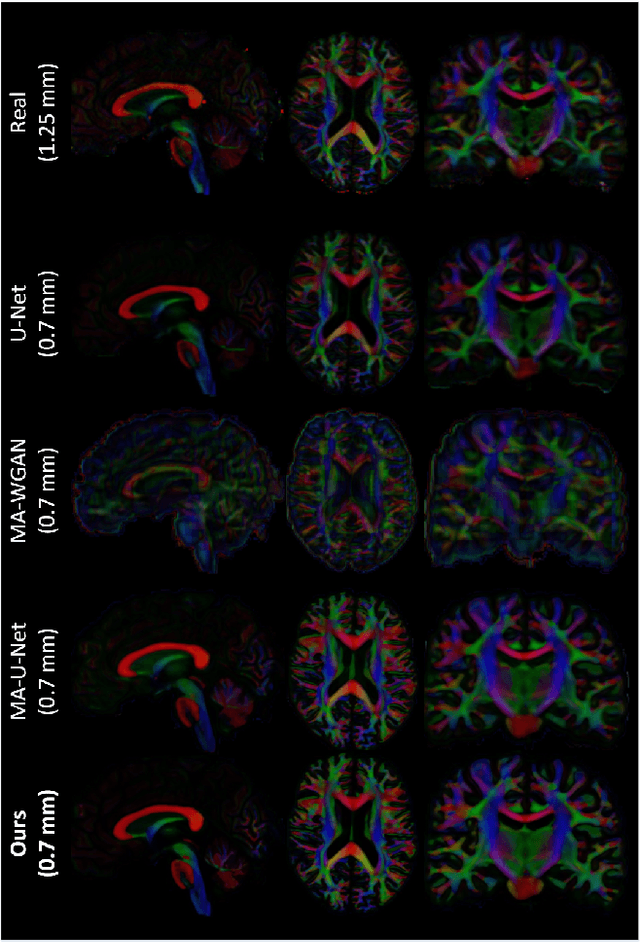

Abstract:The physical and clinical constraints surrounding diffusion-weighted imaging (DWI) often limit the spatial resolution of the produced images to voxels up to 8 times larger than those of T1w images. Thus, the detailed information contained in T1w imagescould help in the synthesis of diffusion images in higher resolution. However, the non-Euclidean nature of diffusion imaging hinders current deep generative models from synthesizing physically plausible images. In this work, we propose the first Riemannian network architecture for the direct generation of diffusion tensors (DT) and diffusion orientation distribution functions (dODFs) from high-resolution T1w images. Our integration of the Log-Euclidean Metric into a learning objective guarantees, unlike standard Euclidean networks, the mathematically-valid synthesis of diffusion. Furthermore, our approach improves the fractional anisotropy mean squared error (FA MSE) between the synthesized diffusion and the ground-truth by more than 23% and the cosine similarity between principal directions by almost 5% when compared to our baselines. We validate our generated diffusion by comparing the resulting tractograms to our expected real data. We observe similar fiber bundles with streamlines having less than 3% difference in length, less than 1% difference in volume, and a visually close shape. While our method is able to generate high-resolution diffusion images from structural inputs in less than 15 seconds, we acknowledge and discuss the limits of diffusion inference solely relying on T1w images. Our results nonetheless suggest a relationship between the high-level geometry of the brain and the overall white matter architecture.